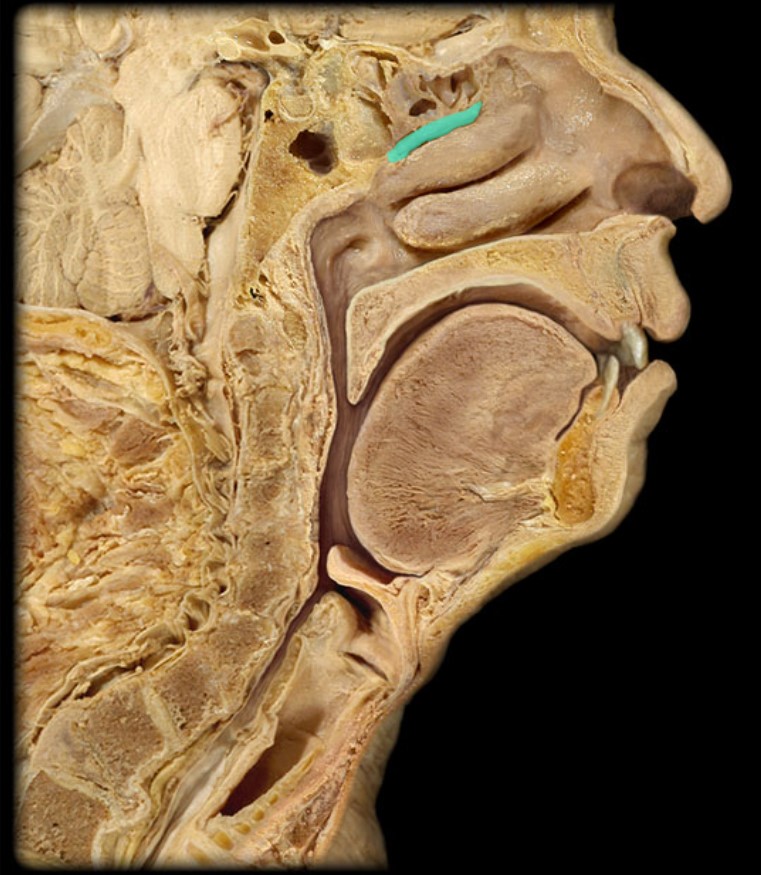

Auditory Hiatus

Torus Tubarius

Sphenoid Sinus

Middle Nasal Concha

Superior Nasal Concha